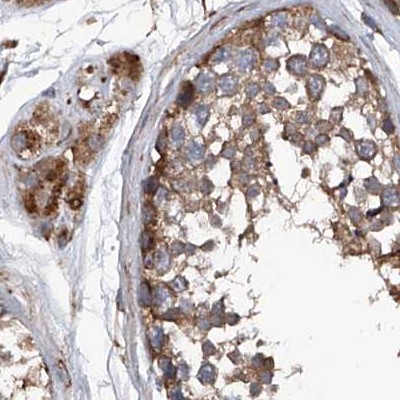

Immunohistochemical staining of human cerebral cortex, colon, lymph node and testis using Anti-ASCC3 antibody HPA031610 (A) shows similar protein distribution across tissues to independent antibody HPA031608 (B).